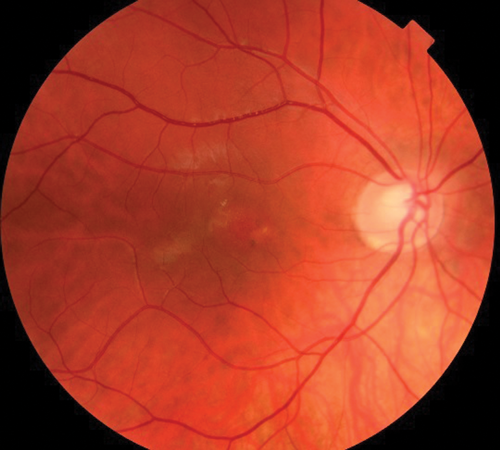

RE funduscopy in Figure 4 reflects a complete resolution of the lesion with patient totally asymptomatic.

Figure 4: RE funduscopy after successful treatment.